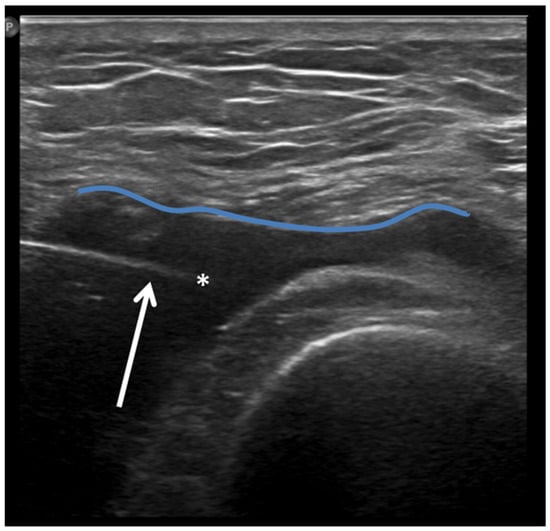

Ultrasound (US) imaging has not traditionally been used as part of the clinical pipeline for OA diagnostics. However, when examining the scientific literature, its role has risen steadily during the last two decades. US assessment of joints offers several advantages, including the ability to assess soft-tissue changes associated with OA and to outline the contour of the bony surface surrounding the joint [64,65]. In addition to detecting structural OA changes, a US can provide insights into inflammatory findings, complementing traditional CR imaging [66]. Several inflammatory findings (e.g., joint effusion/Baker cyst, synovial thickening, and hyper-vascularity), easily detectable throughout a US, are associated with pain exacerbation and disease progression in knee OA (Figure 2, Figure 3 and Figure 4).

Figure 3.

Ultrasound image (Power-Doppler) longitudinal, lateral suprapatellar view showing synovial inflammatory foci with inflammatory hyperemia (arrow).